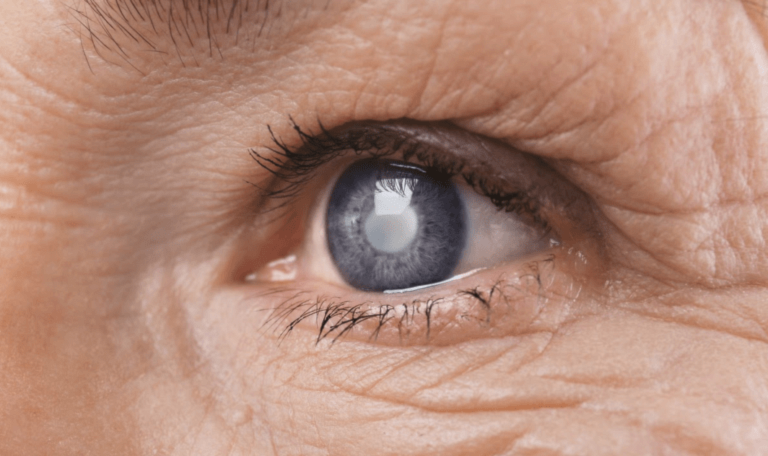

واعتلال الشبكية هو المصطلح الطبي الذي يشير إلى تلف الأوعية الدموية التي تغذي الأنسجة الحساسة للضوء في الجزء الخلفي من العين، ويؤدي انقطاع تدفّق الدم إلى هذا النسيج إلى حدوث عمليات تنكسية، والتي بدورها تؤدي إلى ضمور العصب البصري والعمى الذي لا رجعة فيه.